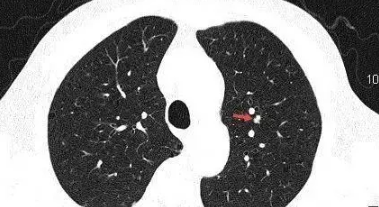

极少数可由肺部恶性肿瘤引起,如出现了毛刺、分叶、胸膜凹陷征、空泡血管征等等。在这种情况下,有必要进一步明确诊断。肺结节6mm应首先考虑肺部感染,抗感染两周后即可复查。如果没有变化,则有必要定期复查,尤其是40岁以上、长期吸烟、长期处于二手烟环境中、或有恶性肿瘤家族史的患者。如果在复查过程中发现某些恶变迹象,必须进一步检查,以便早期诊断和治疗。